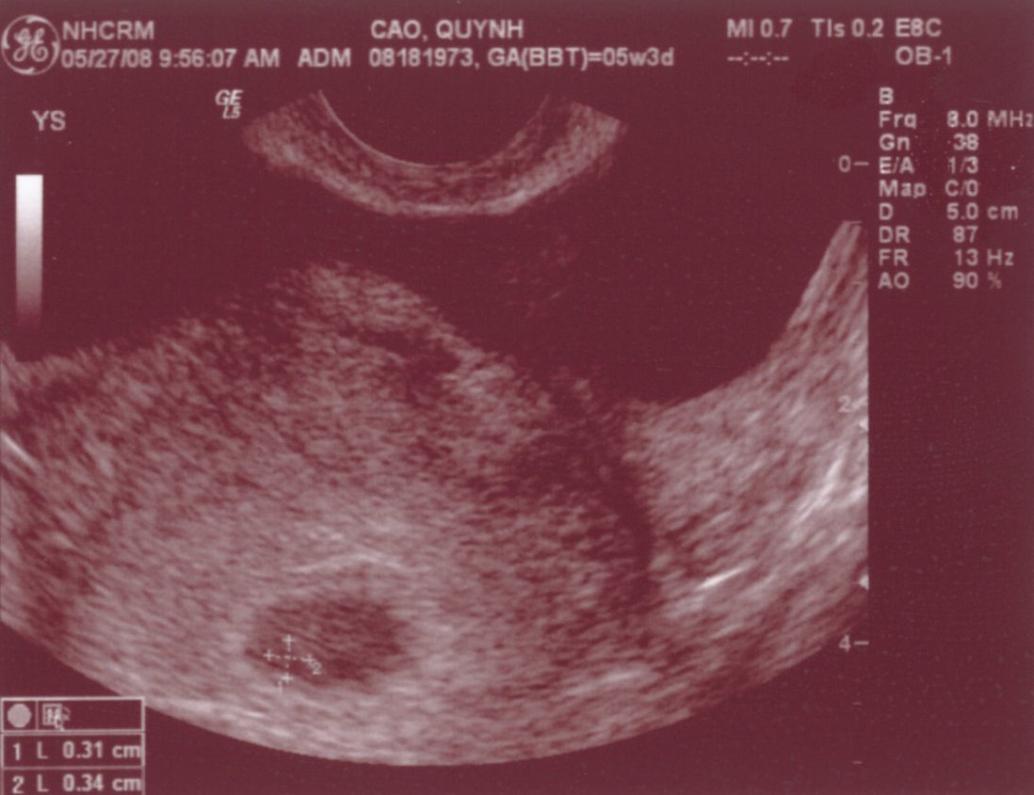

Ngày 11/28/1999 Ba Mẹ có nhau, lúc đó con ở đâu ha? Ngày 5/27/2008, con đây rồi!!! Mới được 2 tuần, là hạt nhân nhỏ xíu trong bụng Mẹ thôi Ngày 6/4/08, lần đầu tiên Ba Mẹ nghe tim con đập, 124 nhịp/phút. Mẹ sung sướng nhìn con. Còn Ba thì rơm rớm nước mắt, hihi!! Ngày 7/8/2008, con được 11 tuần rồi, bắt đầu có tay chân rồi đây... 1 tuần sau tay chân con đã dài ra rồi, lẹ ghê... ...biết nhào lộn vòng vòng nữa, mới nằm úp giờ nằm ngửa rồi. Ngày 9/3/2008, Mẹ chưa muốn biết con là trai hay gái vì muốn bất ngờ, nhưng rồi cuối cùng cũng không đợi được... ...hihi, cục cưng của Ba Mẹ là con trai. Con trai miệng bự giống Ba.  19 tuần là mắt mũi miệng đầy đủ hén. Từ khi biết có con, Mẹ nhờ Ba chụp hình hai mẹ con mình. Cái này là lúc con được 2 tháng trong bụng Mẹ.. ...24 tuần, con bắt đầu cựa quậy lung tung mỗi ngày... ...36 tuần, có lúc Ba Mẹ tưởng đã mất con nhưng con vẫn lớn giỏi ngoan... ..39 tuần, con nặng quá rồi nhưng Mẹ vẫn muốn con ở trong đó thêm chút nữa cho lớn lớn... Ba thì nôn gặp con quá, ngày nào Ba cũng nói chuyện với con.  Bụng Ba cũng bự rồi nè! Ngày 1/20/2009, con 39 tuần, bác sĩ muốn con ra sớm cho an toàn.  Ba Mẹ hồi hộp đợi tới lúc gặp con... Sau gần 8 tiếng chờ đợi thì con ra đời!! Con mở mắt nhìn Mẹ như là biết rồi đó.  Thương con ghê nơi! 1 tuần tuổi thì rụng rún.  2 tuần tuổi thì chụp hình lần đầu với Mẹ, nhỏ xíu xiu xiu... 7 tháng (8/2009) con bò lung tung, chụp hình mà không yên... 14 tháng (4/2010) con chỉ muốn chạy chơi thôi, Ba chụp lẹ lẹ nghe. Ngày 2/19/2010 Ba Mẹ làm lễ cưới ở nhà thờ.  Lần này thì có con rồi.  Có con Ba Mẹ có tất cả...